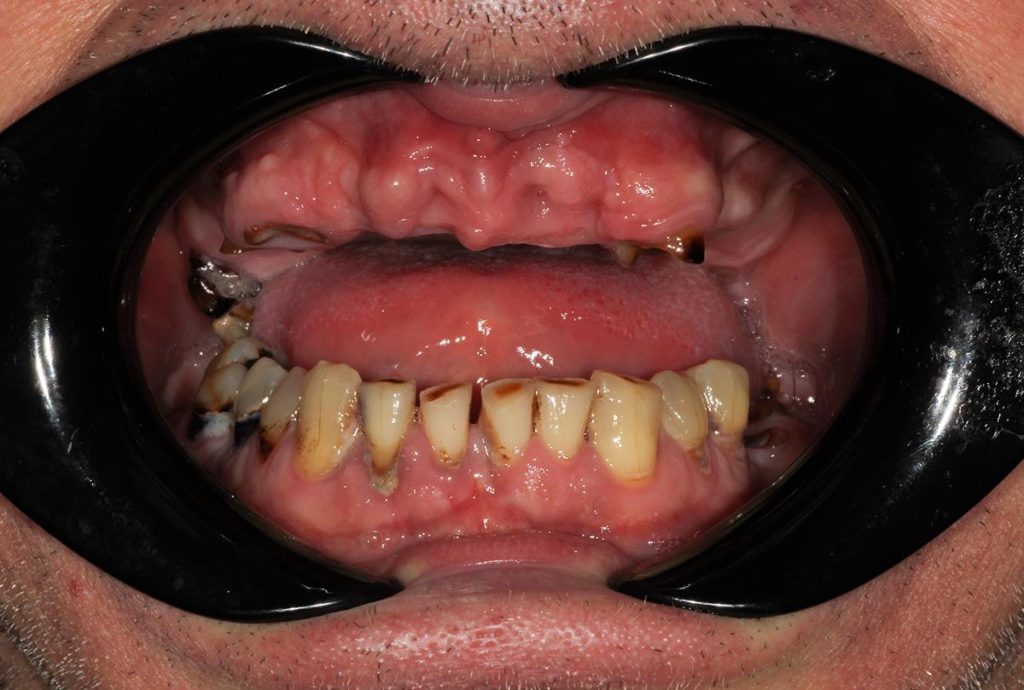

Przeprowadziliśmy precyzyjne leczenie implantologiczne, wszczepiając 11 implantów w szczęce i żuchwie. Konieczna była też regeneracja kości. Po 6 miesiącach gojenia nastąpiła odbudowa pełnołukowa. Kształt, kolor i ustawienie zębów zostały dobrane oraz wykonane na indywidualne życzenie Pacjenta.

Leczenie chirurgiczne i implanto-protetyczne przeprowadził lek.stom. Michał Badowski.